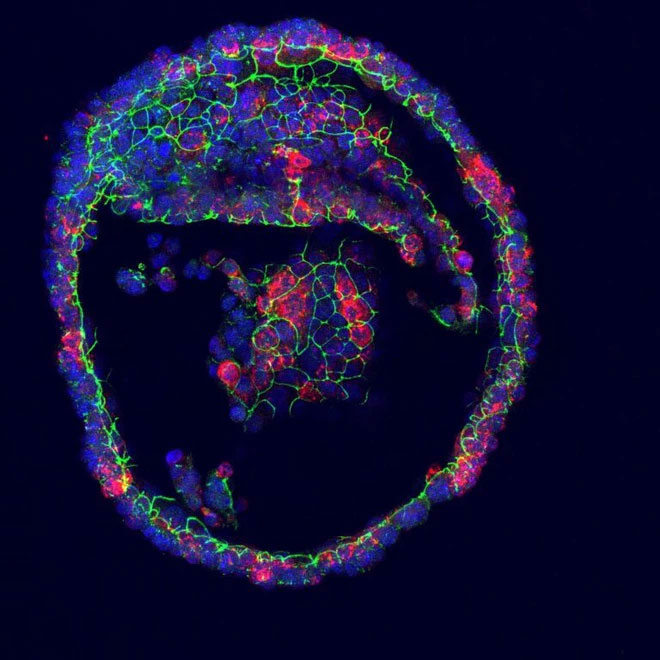

Tuyến lệ nhân tạo được nuôi dưỡng trong phòng thí nghiệm.

Từ các tế bào gốc đa năng trưởng thành, lần đầu tiên họ đã phát triển được các mô tạo thành một cơ quan mang đầy đủ các bộ phận và chức năng của tuyến lệ. Sau khi được cho tiếp xúc với norepinephrine, một chất dẫn truyền thần kinh kích hoạt tiết nước mắt, các tuyến lệ nhân tạo này đã phòng lên như một quả bóng và chúng bắt đầu "khóc".

Ngoài ra để chắc chắn, các nhà nghiên cứu cũng đã tiến hành giải trình tự mRNA để tạo ra một bản đồ tế bào trong tuyến nước mắt của con người. Qua đó, họ đã xác định được 2 loại tế bào khác nhau là tế bào ống dẫn và tế bào túi lệ có trong tiểu cơ quan nhỏ bé của mình.

Các tế bào tuyến lệ (màu đỏ) giúp bạn tạo ra nước mắt.